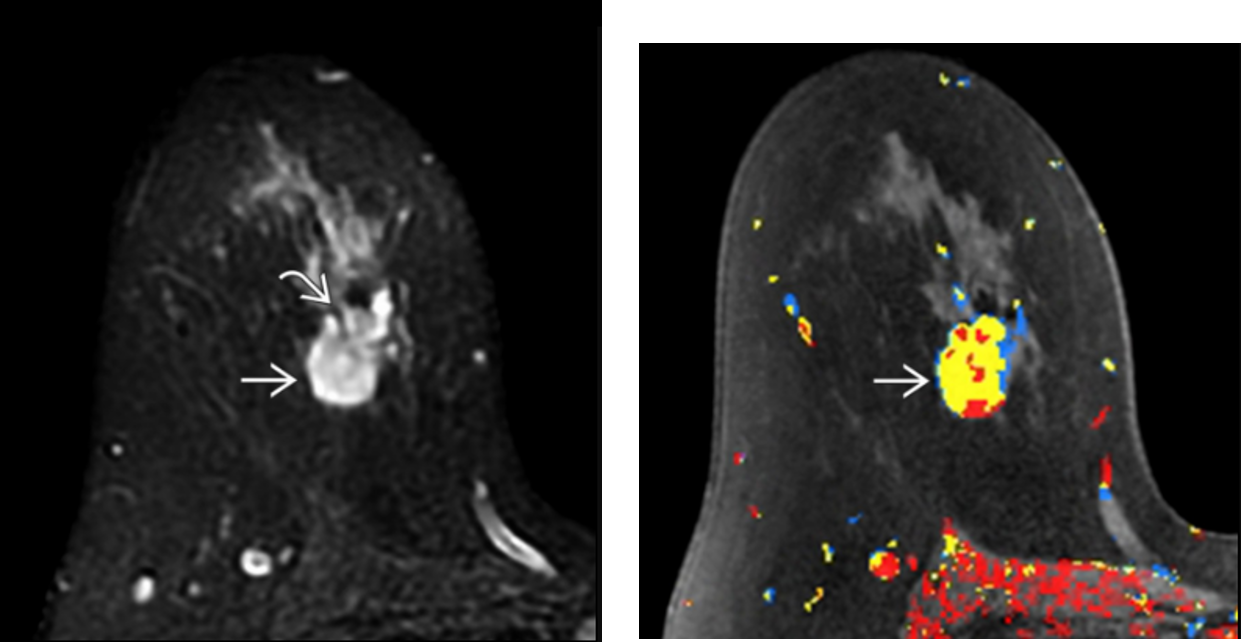

Inflamed cyst

MR: T2-hyperintense, oval or round mass; slow, persistent, uniformly thin rim (not nodular or irregular) enhancement

mucinous carcinoma/colloid carcinoma

-subtype of IDC

MR: Characteristic high-signal T2/STIR due to high mucin content; avid, slow rim enhancement